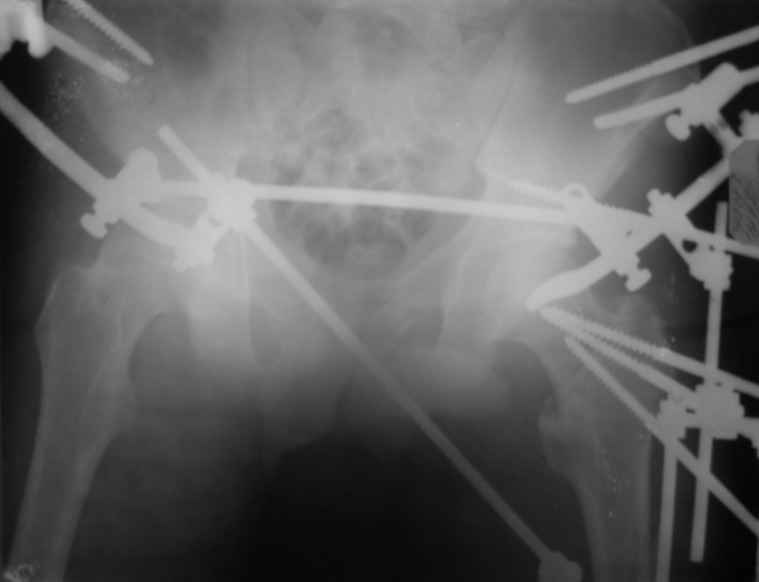

Вот снимки по свежей ситуации, парень 19 лет, длинный оскольчатый перелом бедра от шейки до в-с/3. давно уже ходит на своих ногах.

Представленные Вами рентгенограммы действительно являются примером качественной фиксации спице-стержневым аппаратом. Они, как ни что другое, многое иллюстрируют.

Кроме того, было бы ошибкой ставить знак равенства между нашим и Вашим пациентами. Они не только не похожи, разница между ними просто огромная. Говорю это не для того, чтобы задеть Вас или обидеть. Ни в коем случае. Просто теперь я понимаю, что Ваше мнением строится на простом преломлении Ваших подходов к лечению пациентов со свежими переломами, на ситуацию, абсолютно несопоставимую, подобную нашей.

Компоновку данного аппарата, в котором дистальный отломок фиксирован лишь на дистальном уровне, а проксимальный вообще сам по себе никак, только через бывший сустав, назвать стабильной никак нельзя. Нет стабильности - нет нормального заживления, но есть осложнения, надеюсь, это-то можно экстраполировать на вашего больного?